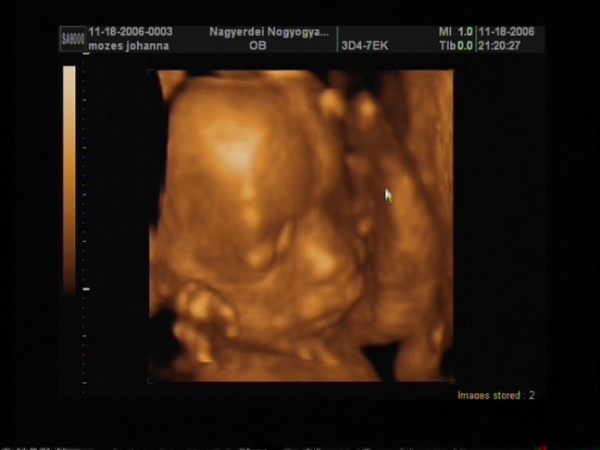

de azért bevallom a kép tényleg kicsit csalóka

azért élőben nem látszik ekkorának!!